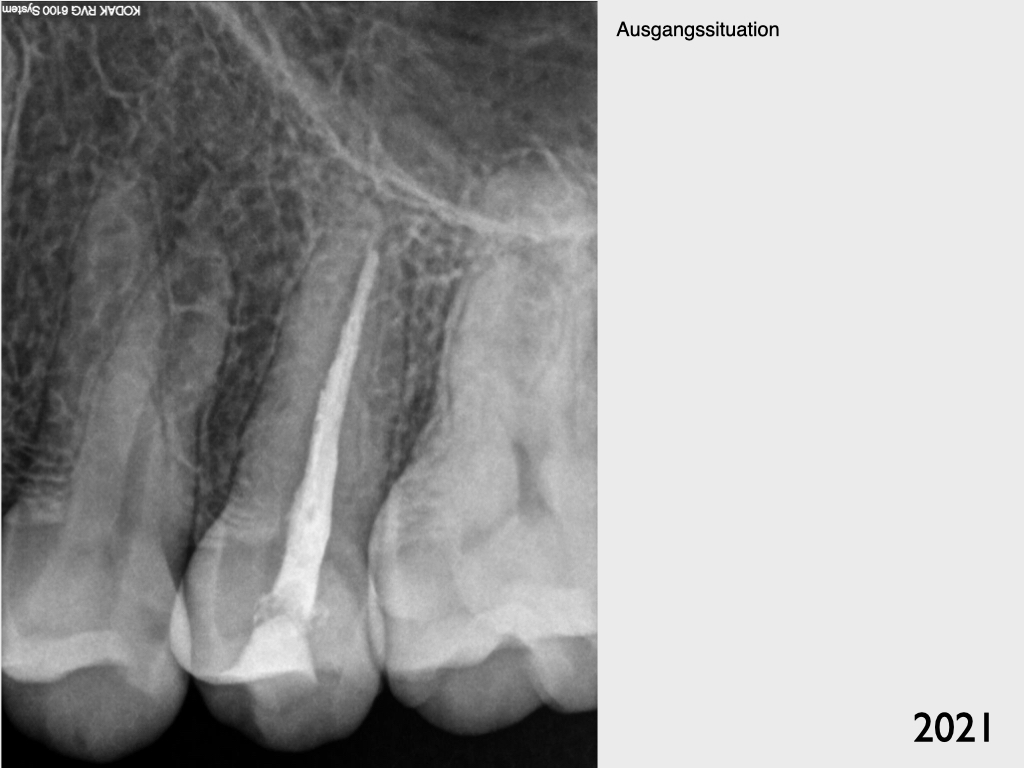

7618.001

Recall 7 Jahre